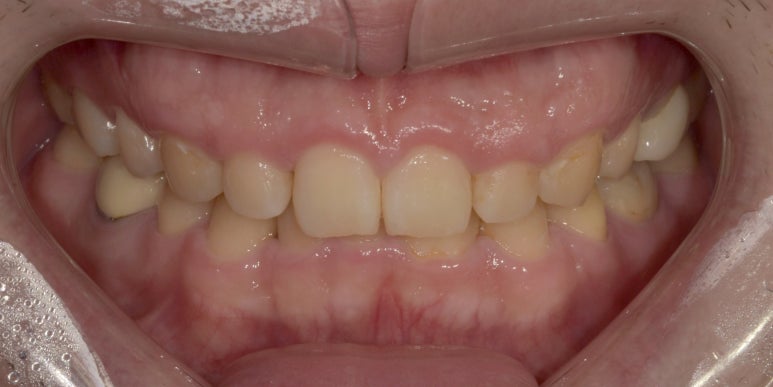

잇몸성형 전후 사진

(전) 2023-05-22 (후) 2023-06-05

위 환자분은 전체적으로 잇몸이 많이 내려와 있는데, 특히 상악 측절치 #12, 22쪽 잇몸이 많이 내려와

이를 개선하면서 전체적인 라인까지 위로 올려주는데 중점을 두었습니다.